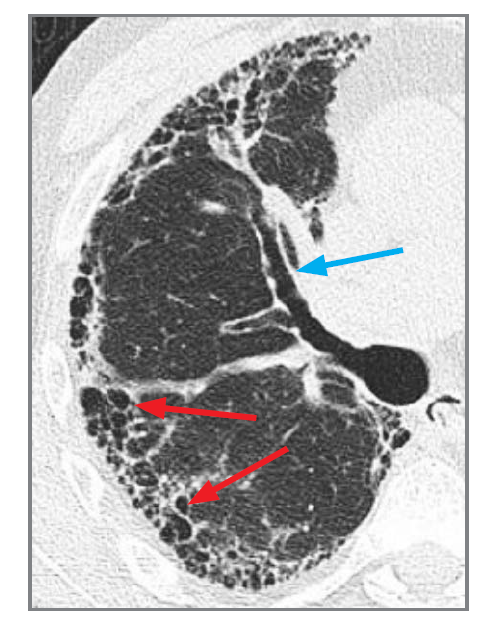

What is this? What feature do we see?

cystic bronchiectasis. ballooning bronchi